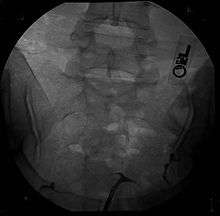

T-shaped uterus

A t-shaped uterus is a type of uterine malformation wherein the uterus is shaped resembling the letter t.[1] This is typically observed in DES-exposed women.[2] It is recognised in the ESHRE/ESGE classification,[3] and is associated with failed implantation, increased risk of ectopic pregnancy, miscarriage and preterm delivery. There is a surgical procedure to correct the malformation.[4]

Women are often diagnosed with this condition after several failed pregnancies, proceeded by exploratory diagnostic procedures, such as magnetic resonance, sonography, and particularly hysterosalpingography.[6][7][8] In such studies, a widening of the interstitial and isthmus of uterine tube is observed, as well as constrictions or narrowing of the uterus as a whole, especially the lower and lateral portions, hence the "t" denomination. The uterus might be simultaneously reduced in volume, and other abnormalities might be concomitantly present.[9]